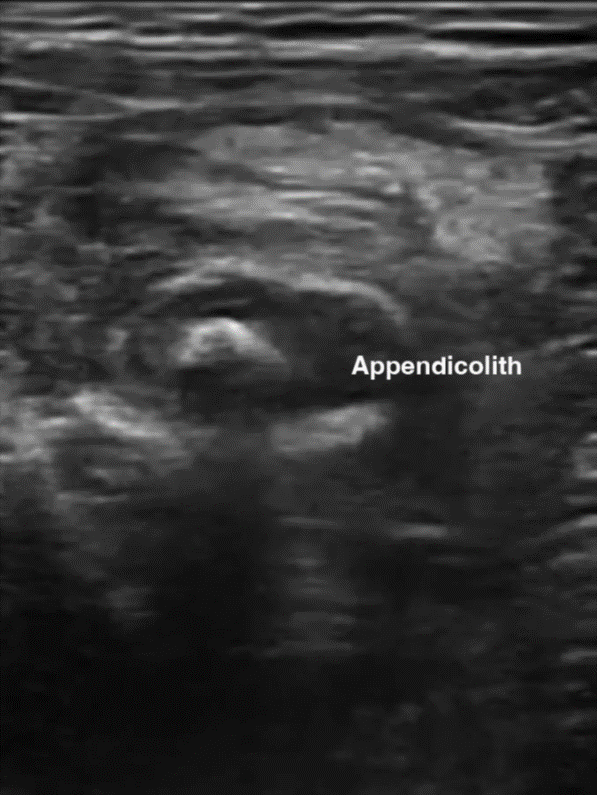

Characteristic sonographic findings include target sign in the short axis, blind-ended pouch in the long axis, lack of compressibility, diameter greater than 6 mm, wall thickness greater than 3 mm, appendicolith, and hypervascularity. Indirect findings suggestive of appendicitis include periappendiceal free fluid or abscess, hyperechoic mesenteric fat, enlarged mesenteric lymph nodes, increased peritoneal thickness, and signs of small bowel obstruction (SBO) [35] (Fig. 6).

Benefits of POCUS examination include lack of radiation exposure, lower costs, and ability to help prioritize radiology studies or expedite surgical consult. It may be particularly useful in centers where radiologist-performed US is not continually available. Visualizing the appendix is often limited by body habitus, pain, retrocecal location, and operator skill and experience. In addition, because a normal appendix is often difficult to visualize, this may be a more challenging POCUS study to learn [9, 34]. POCUS is a promising adjunct diagnostic tool, but it has not been extensively studied as a stand-alone test for appendicitis [34].